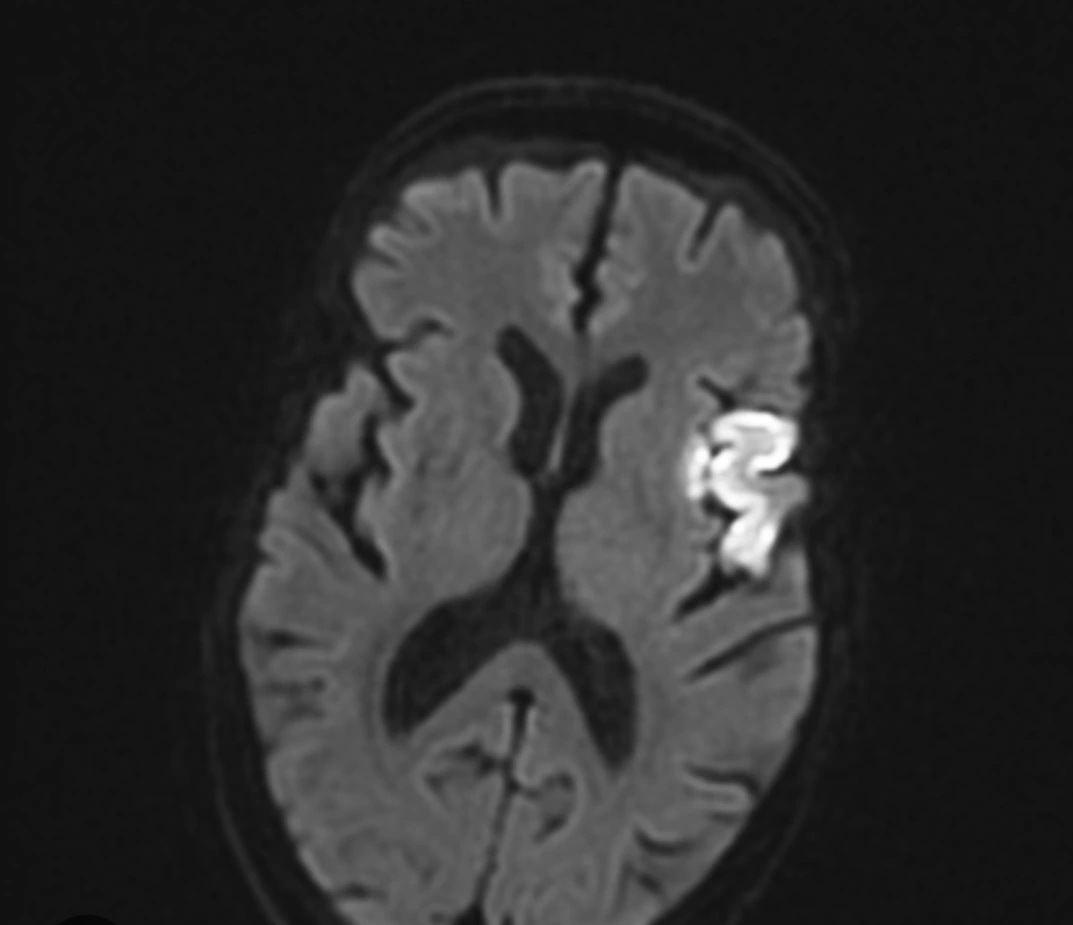

역시.. MRI에서는 예상했듯 Lt. frontal infarction(좌뇌 전두엽 뇌경색) 이른바'Broca's area' 뇌경색. 프랑스의 폴 브로카라는 의사가 간질환자의 뇌를 부검 후 발견한 뒤 명명된 뇌의 해부학적 위치입니다.